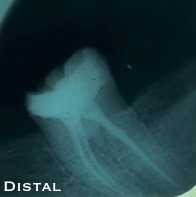

Final x-ray:

- Composite crown.

- Obturation tech. : Single cone with a bioceramic sealer.